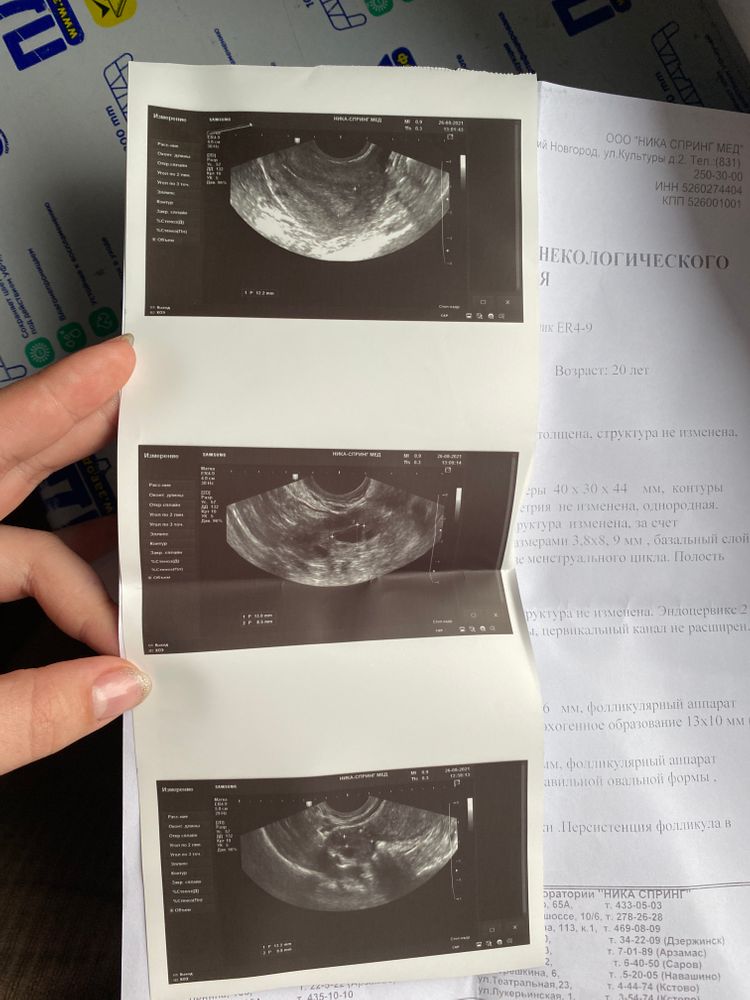

Валерия Никулина, ну смотрите, если у Вас было два ДФ, и на снимке узи не видно фолликулярной кисты (ее там точно нет), то разумно предположить, что у Вас на данный момент два ЖТ (тут не подскажу какого качества, кровоток на Ваших снимках не виден, то надо не по одному снимку смотреть). Ну либо вариант регрессии фолликов.

Чтобы говорить о "остаточном" ЖТ, надо было его, как минимум, иметь с прошлого цикла! Вы, когда смотрели свои ДФ, знали бы о таком однозначно. Значит стоит предположить, что оба ЖТ у Вас свежие, от ДФ идущего цикла.

Теперь далее, 3 дпо, тут только глянуть факт случившейся О, о качестве ЖТ данный дпо не всегда может говорить достоверно. И ЖТ еще подрасти, сформировавшись, может, и просто оставшись в "маленьком" размере, сформировать качественный кровоток и спокойно справляться со своими обязанностями по продуцированию прогестерона.

Валерия Никулина, я конечно не узист, но в обоих яичниках гипоэх.образование,почему она пишет о персистенции фоликула? На счёт размера жт 13*10 не так уж и мало. У вас ещё не беременность подтвердили, если она наступит жт начнёт расти, у меня в 5 акушерских недель жт было 12,а в 6 недель 22. Толщина эндометрия в целом для беременности подходит, она также начнёт расти во время беременности. Но узист пишет, что эндометрий соответствует 1 фазе,поэтому я бы не на что не рассчитывала, если наступит задержка, тогда и будете голову ломать.

елена, дело в том ,что она сказала ,что жт без кровотока